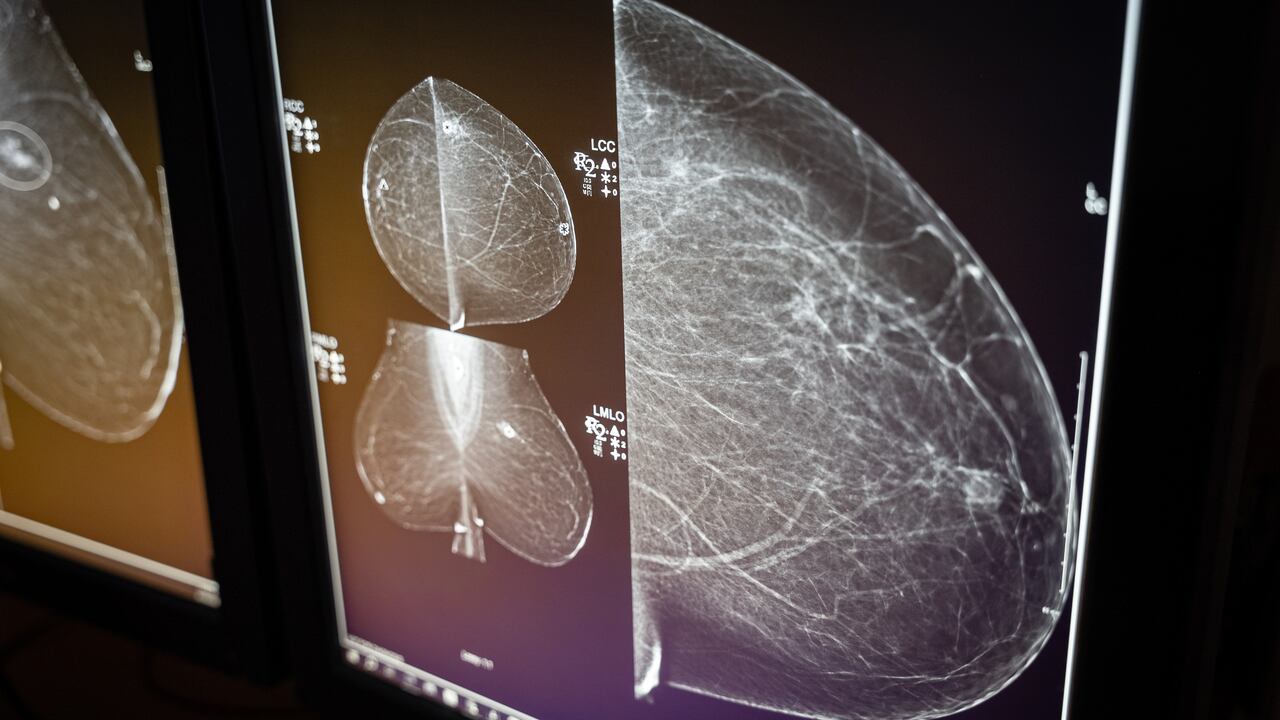

A new study has found that artificial intelligence (AI) could play a major role in improving the early detection of breast cancer, offering hope for more effective screening and better patient outcomes. Researchers report that AI-powered analysis of mammograms can identify signs of cancer with higher accuracy than traditional methods, potentially catching tumors earlier when they are more treatable.

The study, conducted in Sweden, involved thousands of women participating in routine breast cancer screening programs. AI systems were trained on large datasets of mammography images to recognize subtle patterns that may indicate malignancy. Results showed that AI-assisted screening improved detection rates while also reducing false positives, meaning fewer women underwent unnecessary follow-up procedures.